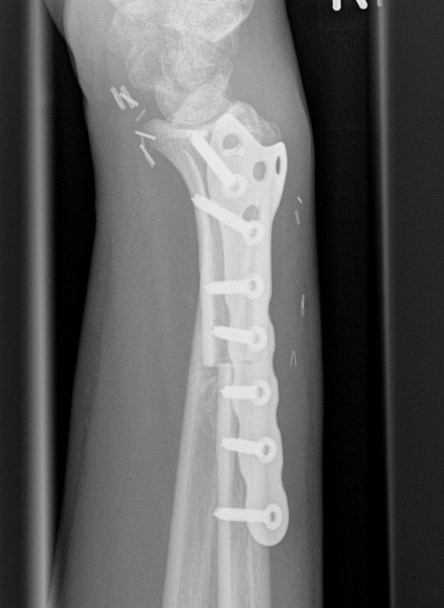

Wide resection and Allograft / Prosthesis Reconstruction

Indications

- extensive soft tissue tumour

- extensive cortical destruction

- impossible joint salvage

- multiple recurrence / failure bone cement

Distal Radius

Abuhejleh et al Eur J Orthop Traumatol Surg 2020

- 57 patients with GCT's of distal radius

- 29% (10/34) recurrence with intra-lesional treatement but no complications

- 4% (1/23) recurrence with wide resection / arthrodesis but 30% complication rate

- increased risk recurrence for Grade 3

- wide resection / arthrodesis should be reserved for grade 3

Distal radius GCT treated with en bloc resection and allograft reconstruction, followed by late wrist subluxation